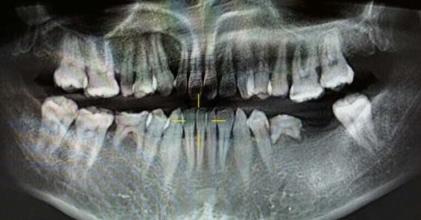

先天性牙齒缺失一般在換牙的時候就能及時發現,但是在小時候沒有及時處理,現在想種牙,一般這種先天性牙還能不能修複呢?深圳牙科醫院醫生表示,常理來說,牙齒從(cong) 缺失後具體(ti) 修複方式有幾種,但是具體(ti) 適合哪種需要檢查牙齒情況後才能確定。 牙齒先天性缺...

先天性牙齒缺失一般在換牙的時候就能及時發現,但是由於(yu) 在小時候沒有及時處理,現在想種牙,一般這種先天性牙還能不能修複呢?深圳牙科醫院醫生表示,常理來說,牙齒缺失後具體(ti) 修複方式有幾種,但是具體(ti) 適合哪種需要檢查牙齒情況後才能確定。